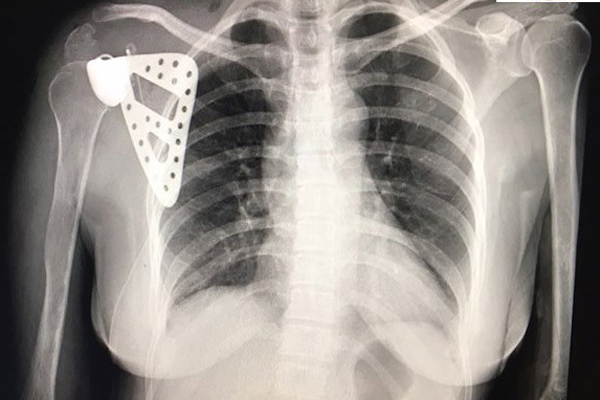

Bác sĩ Việt in xương lắp cho cậu bé 12 tuổi bị ung thư

Cậu bé mới 12 tuổi được phát hiện ung thư xương bả vai, bác sĩ chỉ định phải cắt bỏ toàn bộ và thay xương mới.